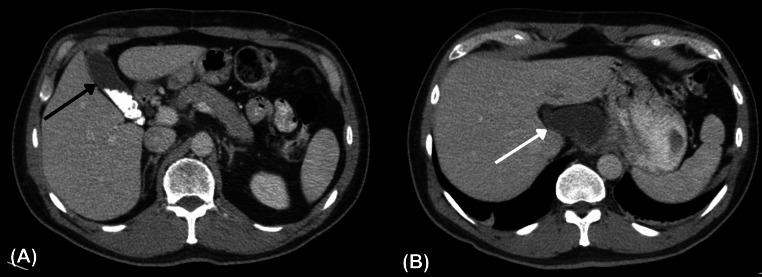

Accessory gallbladders are rare congenital malformations of the hepatobiliary system. They are often incidentally diagnosed preoperatively or intra-operatively. We report a case of a 52-year-old man with an accessory gallbladder that was partially encased by esophageal adenocarcinoma. To the best of our knowledge, this is the first reported case of an accessory gallbladder diagnosed concurrently with esophageal adenocarcinoma. It is important for clinicians and radiologists to be cognizant of this anatomical malformation to avoid misdiagnoses and intra-operative complications.

副胆囊是肝胆系统罕见的先天性畸形。它们常在术前或术中被偶然诊断出来。我们报告一例52岁男性患有副胆囊,该副胆囊部分被食管腺癌包绕。据我们所知,这是首例与食管腺癌同时诊断出的副胆囊病例。临床医生和放射科医生认识到这种解剖学畸形很重要,以避免误诊和术中并发症。